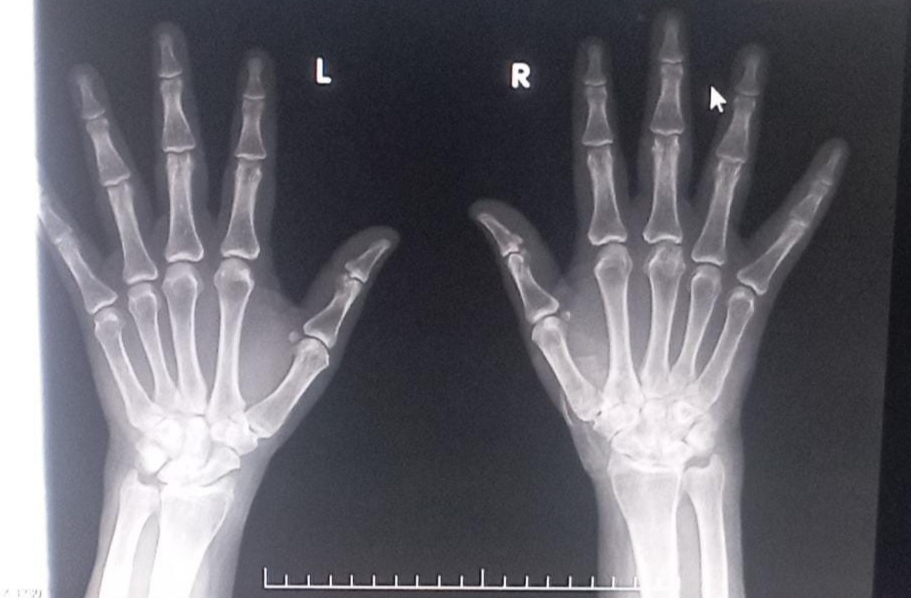

Right hand

local raise of temperature present ,diffuse swelling in wrist and at carpal bones in right hand , tenderness  and restriction of movements present in,wrist, mcp joints  and pip joints

Left hand

Inspection :swelling present

PALPATION:tenderness, local raise of temperature

crepitus cannot be demonstrated

synovial thickening  absent

Range of movements - active - ,restrictedpainful

passive ,restricted ,painful

Clinical images

Orthopaedics refferal was taken in view of joint pain and was diagnosed with GOUT advised TAB. Febuxistat 40 mg po/bd

Asymmetrical Oligoarithritis